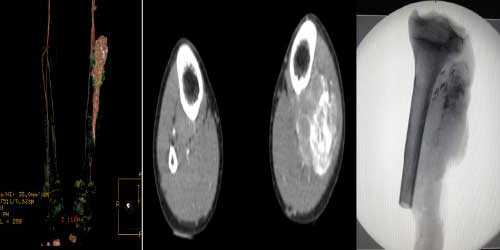

Omurga metastazı, kanserin ilk olarak iç organlarda gelişip daha sonra omurga kemiklerine yayılması sonucu oluşan bir durumdur. Çoğunlukla kan yoluyla sıçrayan bu tür metastaz, hastalarda sırt ve bel ağrısı gibi şikayetlerle kendini gösterir. Erken teşhis ve uygun tedavi yöntemleri, hastaların yaşam kalitesini artırmada kritik bir rol oynar.

Tedavide başarıyı artıran en önemli etkenlerden biri ameliyat öncesi iyi bir hazırlık ve cerrahi planlama yapmaktır. Her şeyden önce tanı doğru konmalı. Bunun için hasta iyi dinlenip, detaylı muayene edildikten sonra tetkikleri dikkatli incelenmelidir.

Her ameliyatın olduğu gibi kemik ve yumuşak doku tümör ameliyatlarının da riskleri vardır. Bu riskleri genel ve yapılan ameliyata özgü olmak üzere kabaca iki başlık halinde gruplandırabiliriz. Öncelikle anestezi ile ilgili risklerin anestezi uzmanı tarafından (...)

Ameliyat sonrası takip ve kontrol hastanın ameliyat masasında uyanması ile başlar. Özellikle damar ve veya siniri ilgilendiren ameliyatlarda hasta ameliyat masasından alınmadan ekstremitenin dolaşımı ve ilgili sinirin fonksiyonu kontrol edilir.